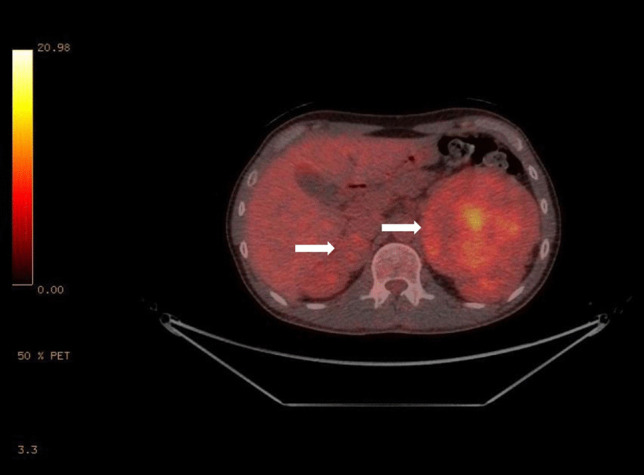

Abstract Image